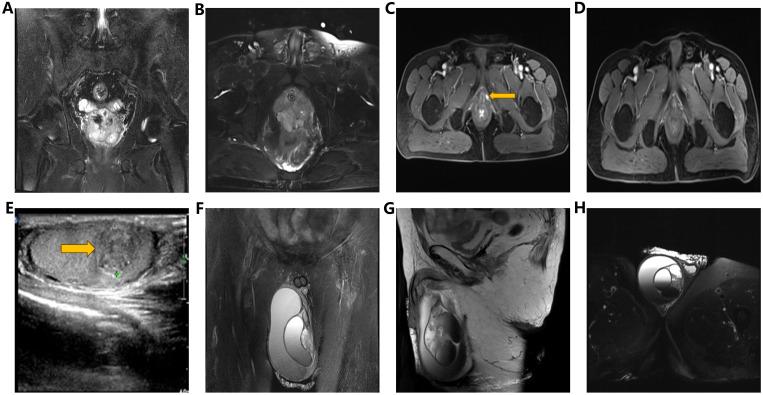

We present the case of a 63-year-old gentleman diagnosed with pure PDA (pT3aN0, Gleason score 4 + 4 = 8), exhibiting a serum prostate-specific antigen (PSA) level exceeding 100 ng/ml. Subsequently, the patient underwent androgen deprivation therapy (ADT) followed by LRP. Subsequently, at 17 months post-LRP, local recurrence and a right testicular mass emerged, prompting pelvic radiotherapy and docetaxel chemotherapy. Ultimately, the patient underwent right orchiectomy 65 months post-LRP, with pathological findings confirming metastatic PDA. Four months post-orchiectomy, PSA levels declined to 1.77 ng/ml. Additionally, a comprehensive review of published literature concerning PDA complicated by testicular metastasis was conducted.

我们报告1例63岁男性患者,诊断为纯PDA(pT3aN0,Gleason评分4 + 4 = 8),血清前列腺特异性抗原(PSA)水平超过100 ng/ml。随后,患者接受雄激素剥夺治疗(ADT),之后行LRP。LRP术后17个月,出现局部复发和右侧睾丸肿块,遂进行盆腔放疗和多西他赛化疗。最终,患者在LRP术后65个月接受右侧睾丸切除术,病理结果证实为转移性PDA。睾丸切除术后4个月,PSA水平降至1.77 ng/ml。此外,还对已发表的有关合并睾丸转移的PDA文献进行了全面综述。